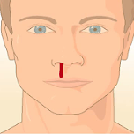

Bloedneus: Oorzaak en behandeling

In deze animatie wordt uitgelegd wat een bloedneus is en wat daarvan de oorzaak is. Ook wordt er aangegeven hoe je het beste een bloedneus kunt stoppen en wanneer je het beste een arts kunt raadplegen voor een behandeling.

Bloedneus bij de huisarts 1

De meeste mensen hebben wel eens een bloedneus gehad. Hoe kun je een bloedneus stoppen? Huisarts Edwin Hut vertelt over de oorzaak van een neusbloeding en welke behandeling je kunt toepassen.

Bloedneus als sportletsel

Bloedneus en eerste hulp

In deze video wordt uitgelegd hoe je hulp verleent bij een bloedneus. De belangrijkste handelingen worden op het einde van de video toegelicht in slowmotion.

Hoe Stop Je Een Bloedneus? Dokter Frans Geeft Advies!

1. Goed snuiten. 2. Knijp je neus dicht, net boven je neusbeen 3. Houd je hoofd iets omlaag, kijk naar beneden. 4. Houd dit 5-10 minuten vol. 5. Nog niet gestopt? Nog een keer 5-10 minuten dichtknijpen.